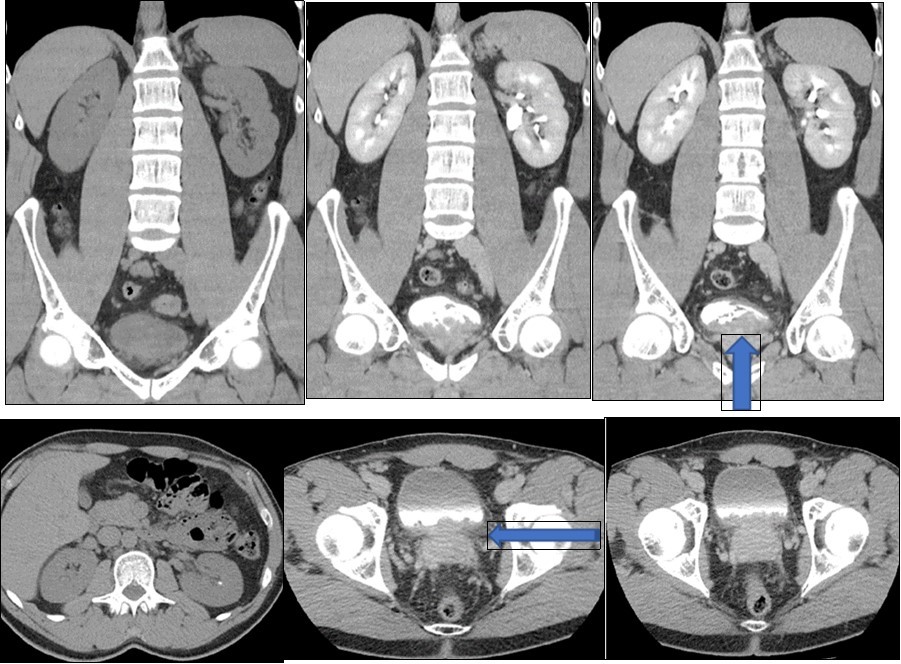

A young 38-year-old man, with no pathological history, consults for cystitis evolving for 4 months. The patient's clinical examination is normal. Laboratory test results and urine studies were unremarkable. The abdomin-pelvic ultrasound revealed an echogenic intra vesical tissue structure of its lower part, 2 cm thick. Thickening of the bladder wall without bilateral ureteropelocalitial dilation. The prostate is normal. The tomodensitometric examination (CT) finds a vegetative mass of the homogeneous bladder floor increasing after injection of contrast product which extends towards the left ureteral meatus without uretero-hydronephrosis. The posterior wall of the bladder is thickened with invasion of the inter vesical-prostatic fat. The rectal perineal fat was respected. No retro peritoneal or pelvic lymphadenopathy (Figure 1). Calculation of the left kidney of 2 mm non obstructive. Kidney function and morphology are normal. Cystoscopy shows a solid, polyp-like lesion covered with normal looking mucosa that has been completely resected.

(Figure 1), vegetative mass of the homogeneous bladder floor increasing after injection of contrast product extends to the left ureteric meatus without uretero-hydronephrosis. The posterior wall of the bladder is thickened without invasion of the inter vesico-prostatic fat (large arrow). The rectal perineal fat was respected. Calculation of the left kidney of 2 mm non obstructive (fine arrow).